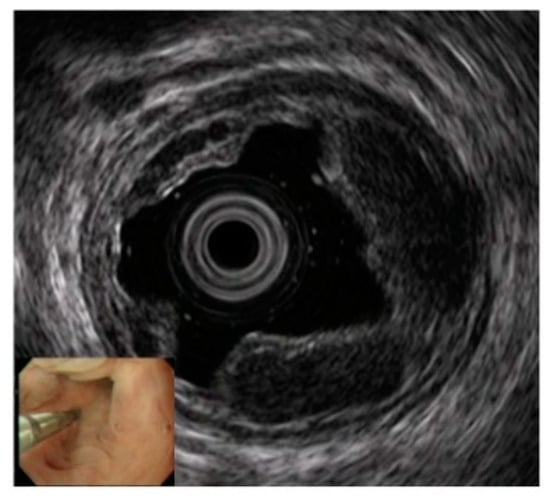

3.2. Observation of Esophageal Varices Using the Endoscopic Technique of Electronic Radial-Arrayed EUS